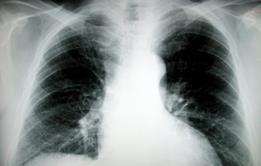

NHS commissioners could save more than £800m over the next decade by improving care pathways for patients with chronic obstructive pulmonary disease, analysis available exclusively to HSJ subscribers suggests.

The analysis by health information specialists Sg2 projects how much COPD patients will cost NHS commissioners in each primary care trust area by 2020. It then sets out for each primary care trust the savings possible through better managing the COPD pathway.

The data is timely as COPD exacerbations are common over winter months, creating capacity issues at hospital providers.

The disease accounts for one in eight emergency admissions in the UK and the second highest number of bed days.

With seasonal capacity issues rising, this quarter’s HSJ Change Forecast focuses on COPD and explores how a proactive approach to care pathway management could save over £800m on COPD inpatient care alone.